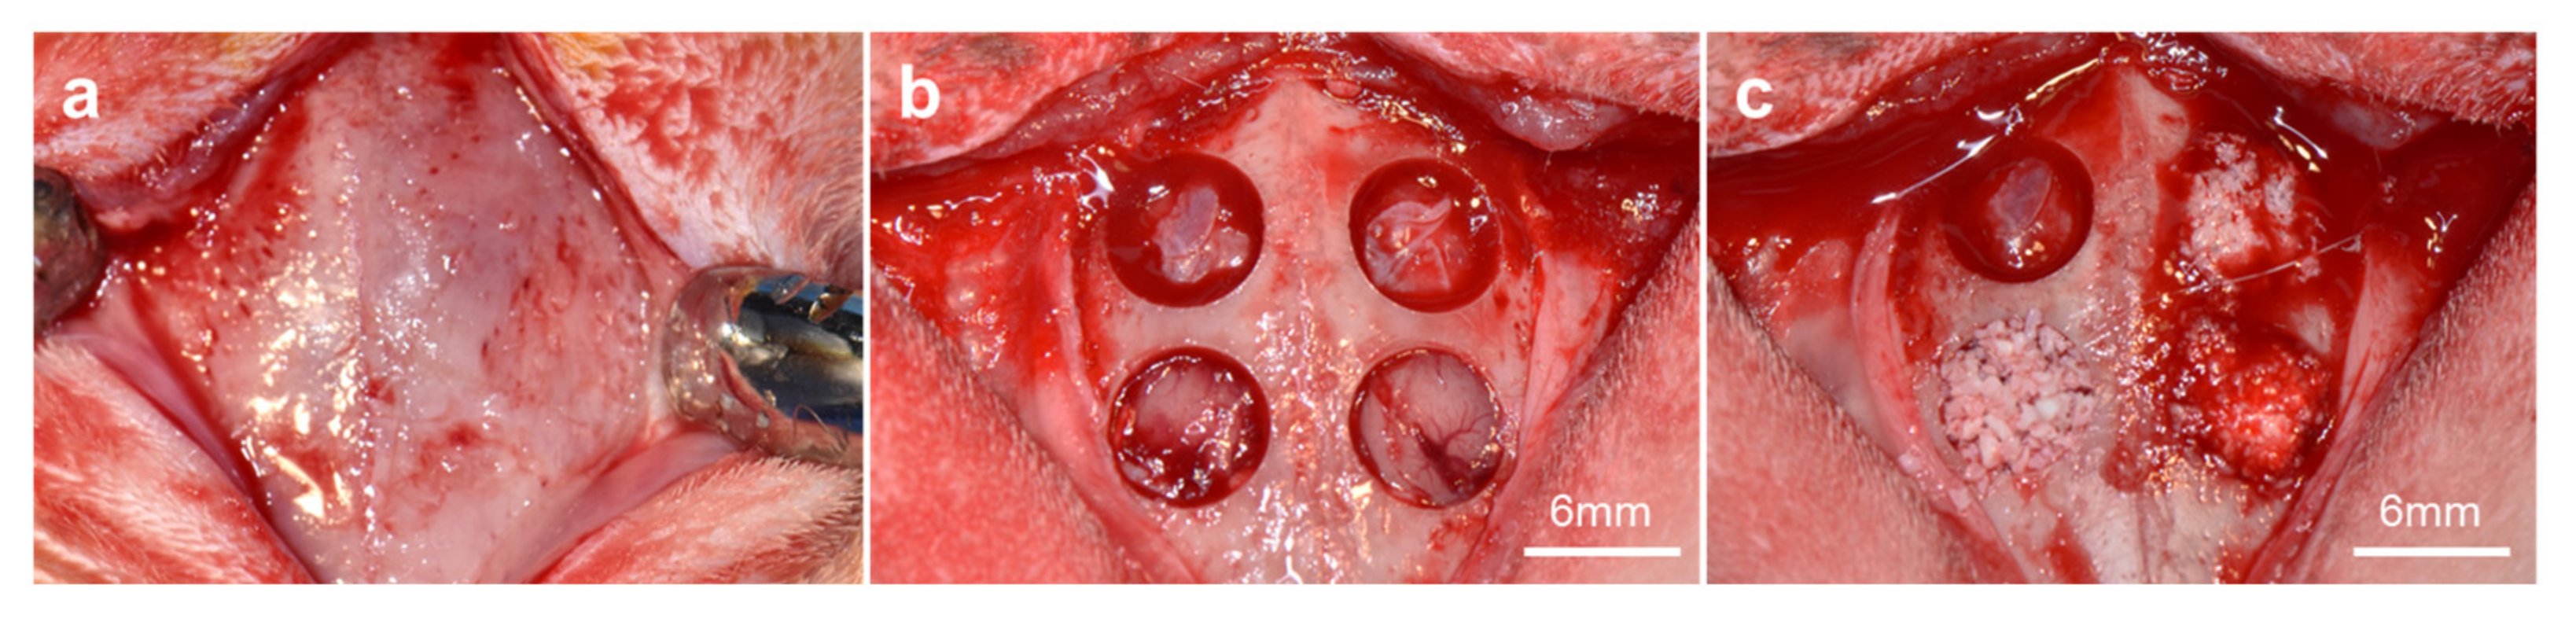

2.3.1. Operative Procedures

3.2.1. Clinical Findings